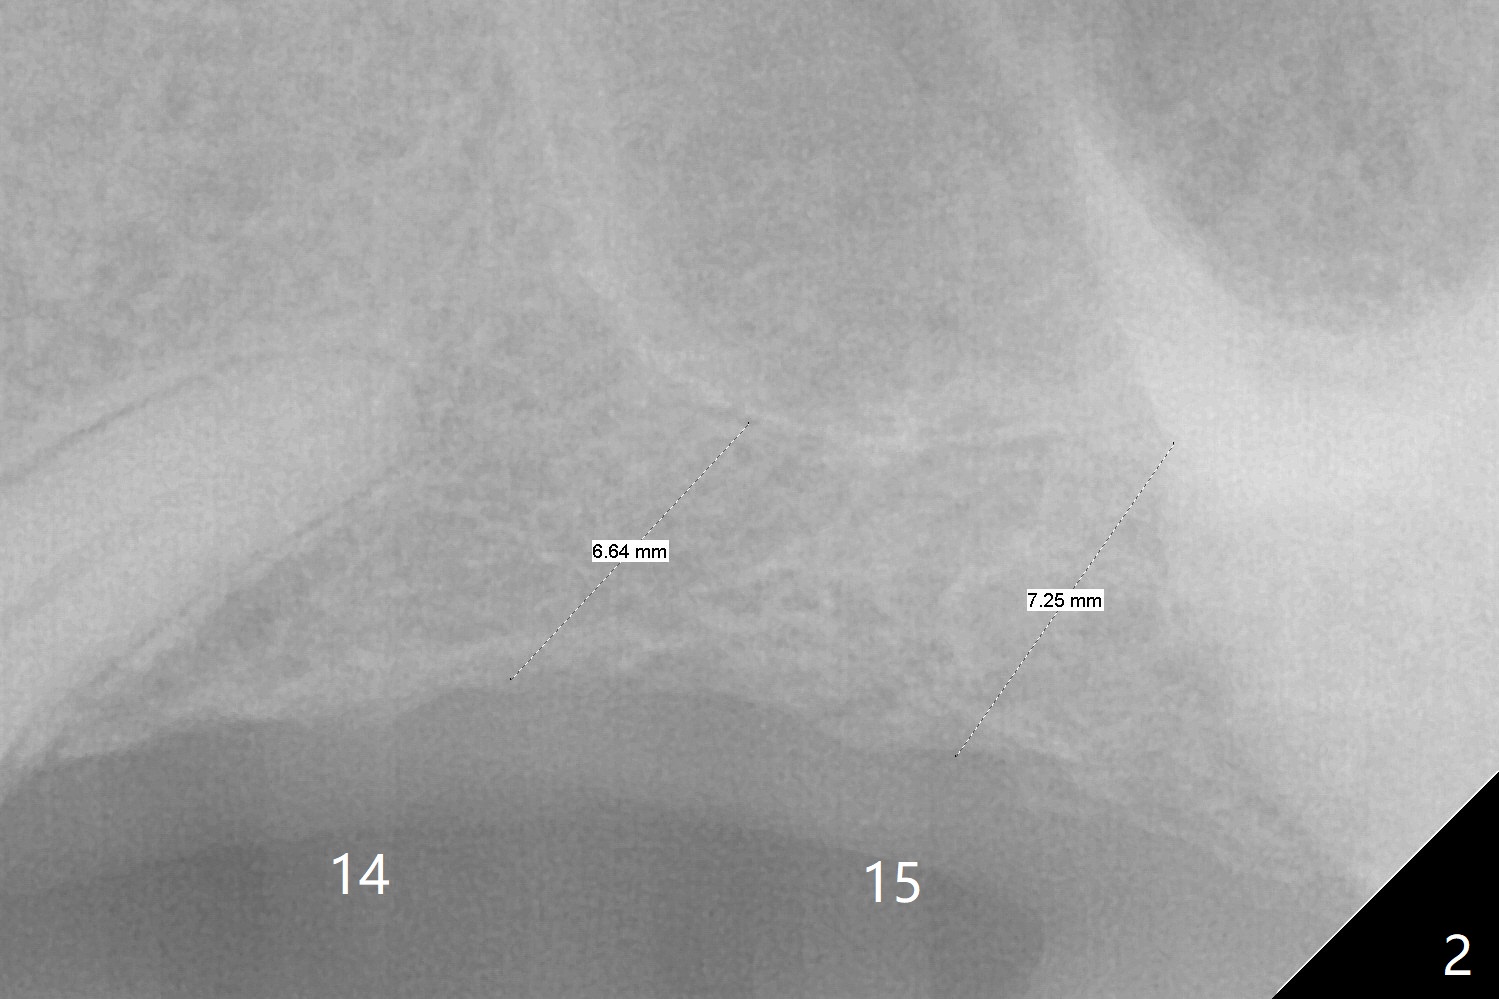

A 66-year-old man with 4 implants in function returns requesting one more at the upper left sextant (Fig.1).  With the opposing implant at #18, two implants at #14 and 15 are necessary.  Can guided surgery be performed with sinus lift (Fig.2)?

With CT, it appears that 5x8.5 and 10 mm implants are to be placed without and with simultaneous sinus lift (Fig.3).  Take photos of the teeth with gingival erythema, as compared to the implants placed.